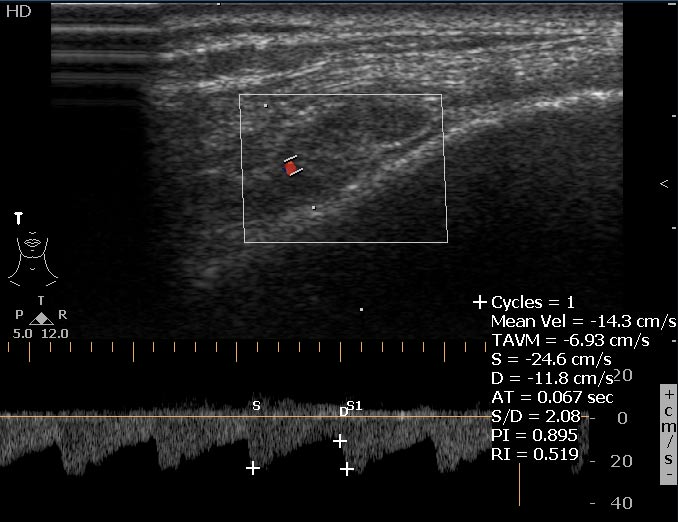

Мужчина 46 лет, жалуется на постоянные боли в правой височной области. В мягких тканях правой височной области пальпируется маленькое болезненное образование.

Сонограммы

Впервые встречаю подобное. Ваше мнение?

Ну вот деталь, которая может быть немаловажной - у пациента подагра, имеются тофусы в ушных раковинах.

На снимке утолщение веретенообразное мышечного слоя с наличием кальцификатов(два) Кальцификаты в мышце чаще встречаются при паразитарных инфекциях(трихиниллез,токсоплазмоз,цистецеркоз),но их больше по количеству и в разных местах.Оссифицирующий миозит-имеет свою картину и распространение.Насчет Хортона-навряд ли,это же поражение сосуда.Насчет тофусов-они содержат ураты,чаще локализуются подкожно(не в мышце),при подагре осификации вдоль сухожилий.А может был удар,гематома с частичной кальцификацией?